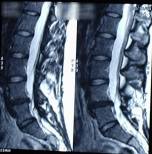

Decompression Therapy is a modern, high tech, non-surgical traction procedure used to treat disabling low back, neck, and radiating leg and arm pain.

This type of therapy is very successful in relieving pain associated with disc herniation and degenerative discs.

By significantly reducing internal disc pressure, spinal decompression promotes retraction of the herniation back into the disc and promotes intake of fluids, oxygen and other substances necessary for healing the disc.